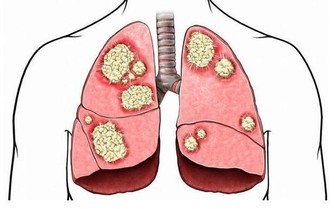

*****2、 呼吸急促*****

心髒病患者除了常見的症狀外,還會出現呼吸急促的問題,會感覺氣不夠用。靜坐幾分鐘後,呼吸似乎恢復正常,但是當患者重新走動時,喘息又開始。這種喘息常常被人忽視,尤其是患有心肺病的老年人。